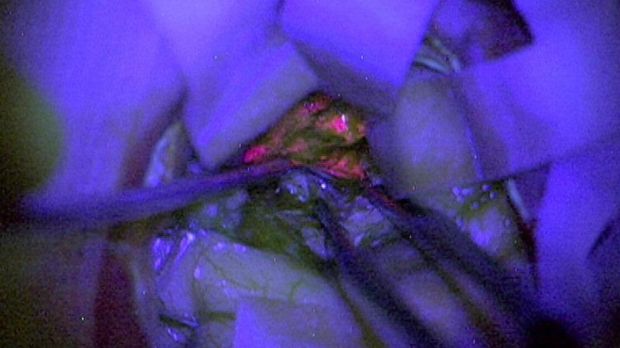

يمكن الاعتماد على الإفرازات وردية اللون في التمييز بين الخلايا السرطانية والأنسجة السليمة في المخ.

رجحت نتيجة تجربة أجراها علماء أن الإفرازات الكيميائية المسؤولة عن اكتساب أورام المخ اللون الوردي قد تساعد في إزالة الأورام السرطانية بأمان.

ويأمل الباحثون في أن تساعد تلك الإفرازات الجراحين على التمييز بين الخلايا السرطانية وأنسجة المخ السليمة.

واستخدم الجراحون مجهرا للمساعدة في رؤية الأنسجة المضاءة أثناء إزالة الأورام من المخ.